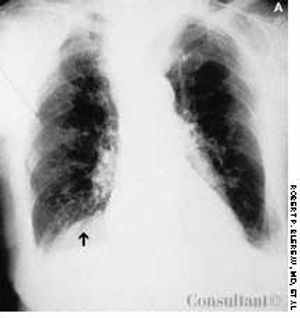

A 95-year-old woman was brought to the emergency department with hemoptysis. Erect posterior-anterior (A) and lateral (B) chest films showed a density at the base of the right lung posteriorly. A CT scan (C) revealed that the mass was the right kidney above the diaphragm and adjacent to the heart. The kidney had migrated through a foramen of Bochdalek.